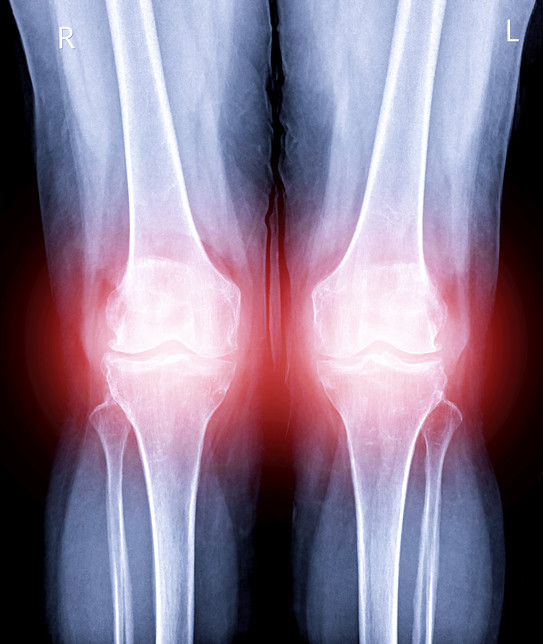

이렇게 쌓인 요산 결정들은 관절이나 연골에서 통증과 염증을 유발한다.

갈수록 증상이 악화되면서 관절이 화끈거리고 붉게 부기가 올라올 수 있다.